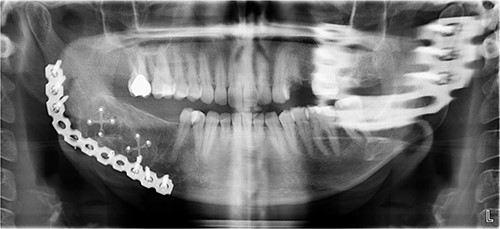

The excised specimen’s histopathology confirmed its benign nature. One year postoperatively, the patient showed no infection or inflammation, with optimal mouth opening and mandibular movement. The reconstruction plate remained stable and intact (Figs 6 and 7).

Postoperative panoramic radiograph demonstrating the reconstruction plate in place after tumor resection and bone grafting.

Follow-up panoramic radiograph showing stable reconstruction plate and no signs of recurrence one year postoperatively.